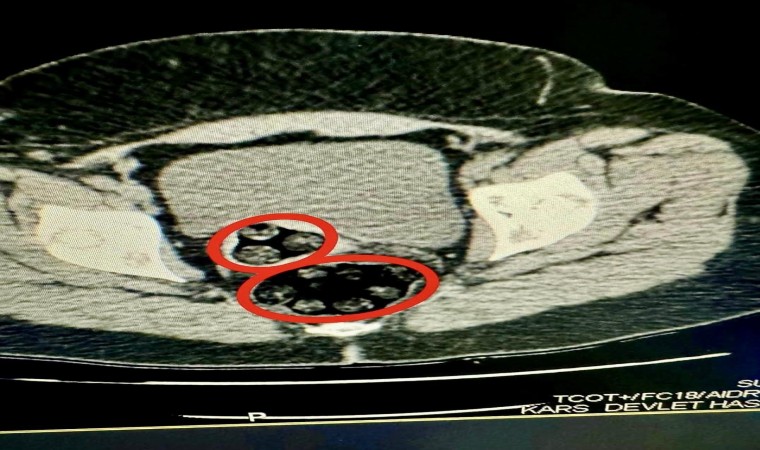

94 parça uyuşturucu cerrahi müdahale ile çıkarıldı

Otobüste gözaltına Fahımeh Golmohammadı Yenkejeh’in yapılan iç beden muayenesinde makadında cisim olduğu tespit edildi. Fahımeh Golmohammadı Yenkejeh’in makadına saklanmış bir şekilde 94 parça 550,63 gram metamfetamin uyuşturucu maddesi cerrahi müdahaleyle çıkarıldı.